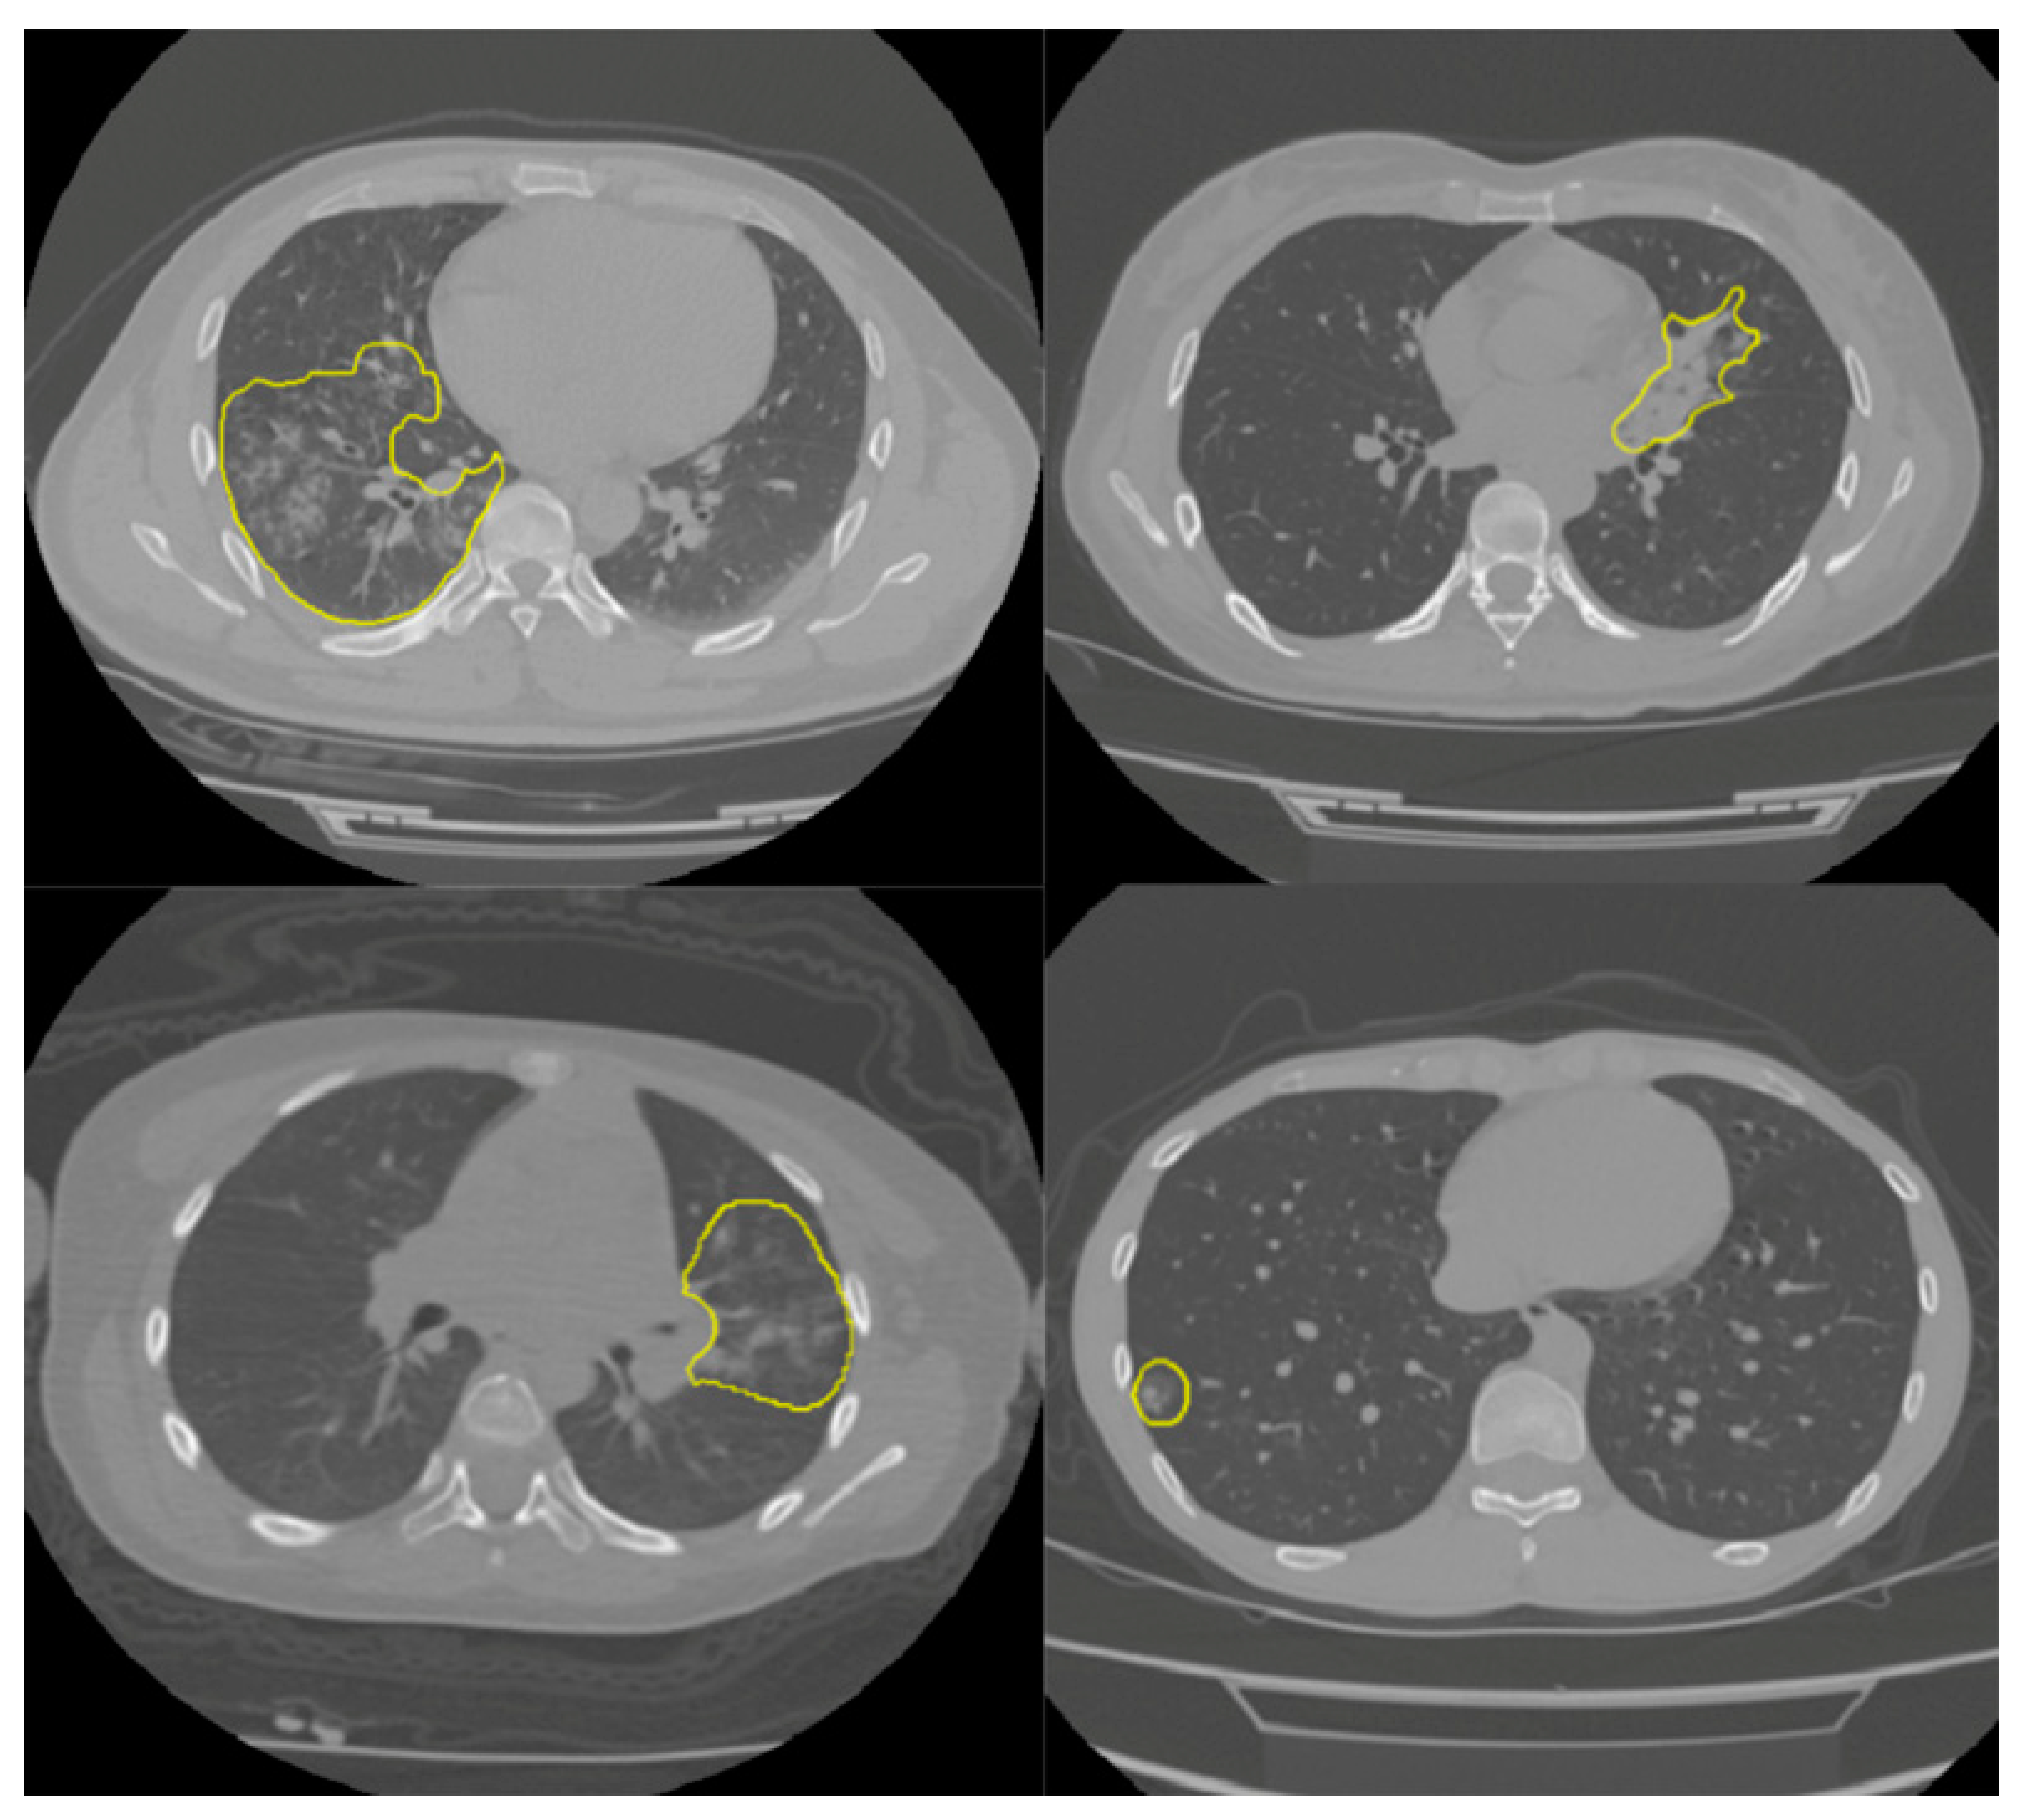

2.1. Dataset